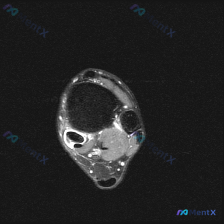

踝关节MRI疑似软组织积液?看完这个分析思路捋顺了

病例核心影像信息

这是一张踝关节MRI矢状位T1加权图像,原始疑问是观察到「软组织液体」,系统影像评估结果如下:

- 骨性结构:各骨皮质连续,无骨折、骨质破坏,骨髓信号均匀,关节对位正常,关节面光滑,无明显骨赘或软骨下囊肿

- 韧带肌腱:跟腱形态信号正常,止点无异常,其他肌腱走行信号无异常,未见腱鞘积液

- 软组织与关节:关节腔内未见明显异常积液信号,皮下肌肉间隙无水肿或异常肿块,跗窦脂肪信号正常